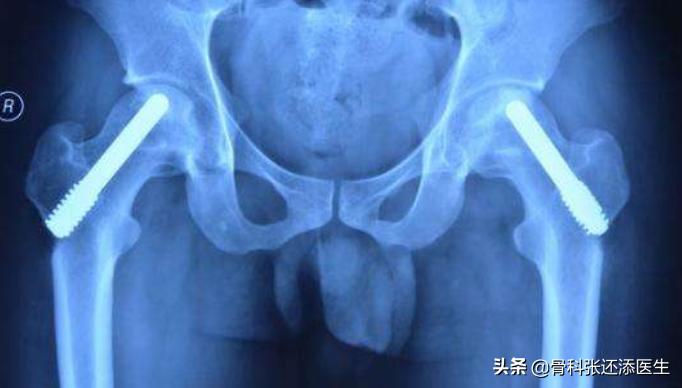

@多孔钽棒(内固定):打在股骨颈及股骨头中间,支撑股骨头,避免塌陷,微创,简单,可负重,是近年比较主流的治疗方式。

钽棒术后x光